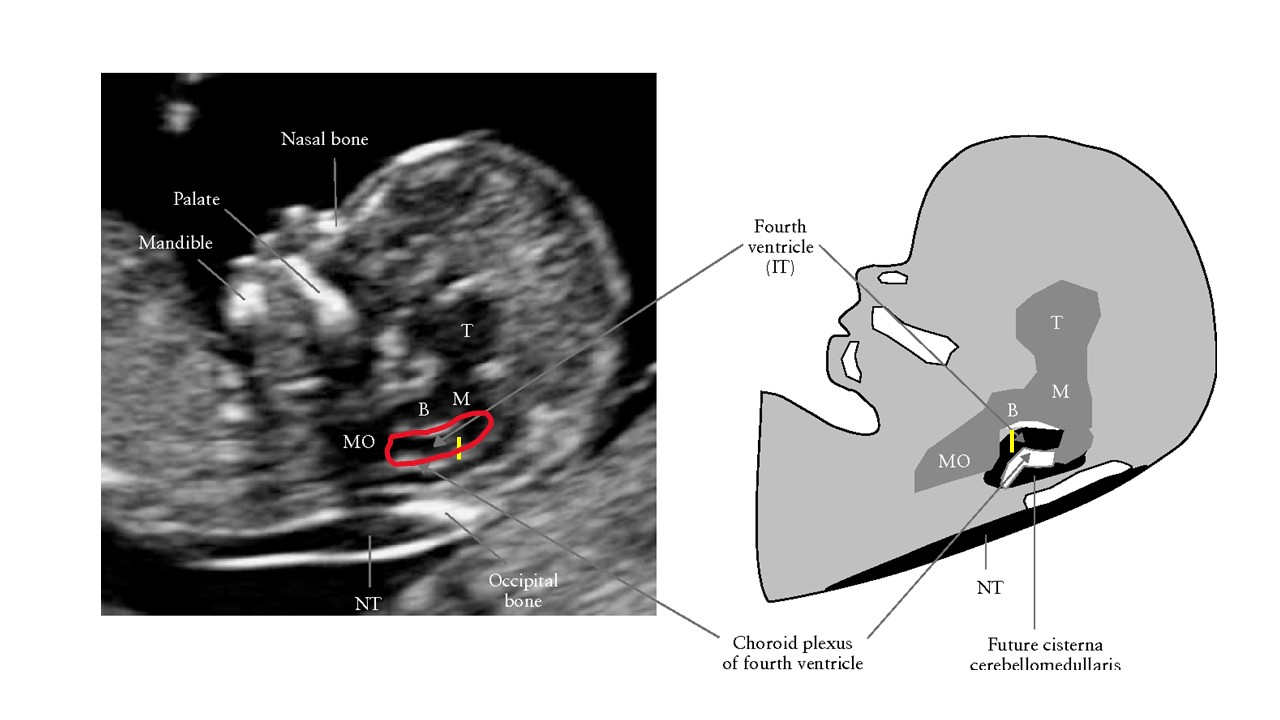

Siêu âm hình thai học quý I

ThS. BS CKII Nguyễn Đình Vũ - Khoa CĐHA, Bệnh viện Hùng Vương